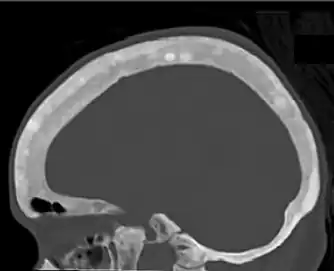

Ground glass density of the skull.[17] -